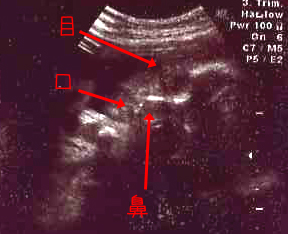

まどろんでるのかな?という表情をしてたベビーたん(分かりづらいけど…)。

30W1D

★頭の大きさ(横幅)7.88センチ

★体重 1734グラム

…体重が激しく増加しています!?

しかしこれも、数百グラム単位で誤差が出るらしいので、あくまで目安なのですが。

生まれてみたらエコーで測定した体重よりも軽かった(重かった)ということはよくある話だそう。